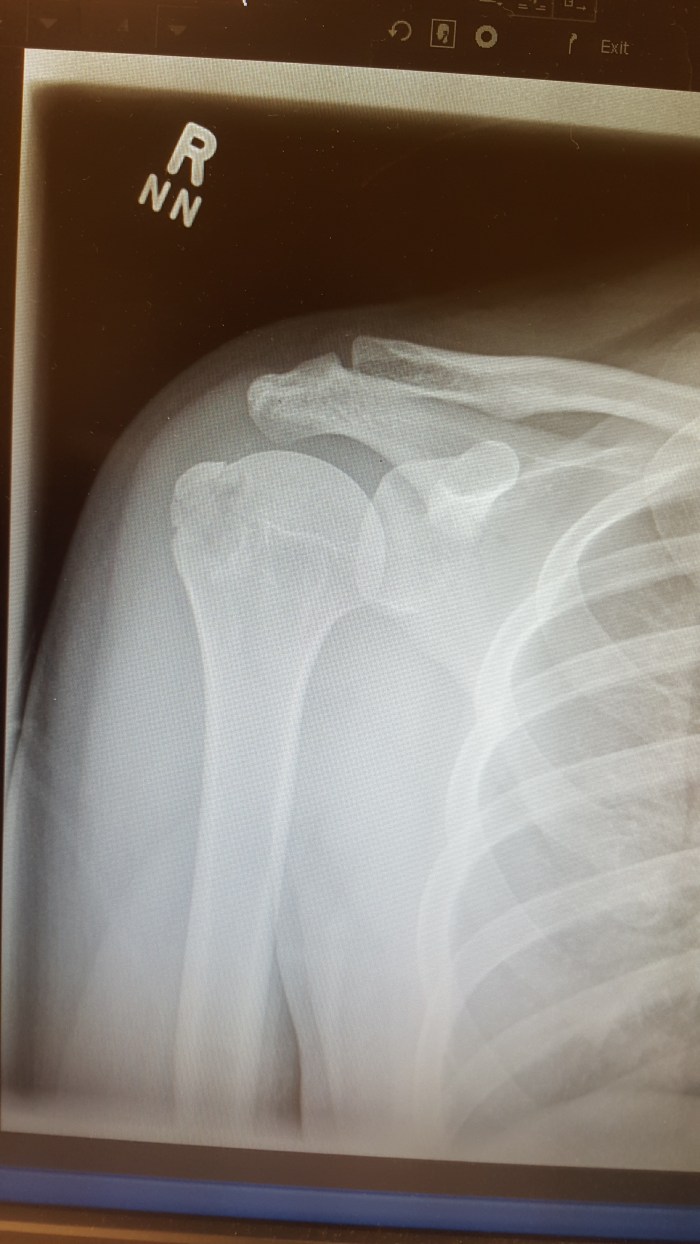

Got x-rayed in Japan for the shoulder, but was told that it was fine. Got back into Canada and got x-rayed in the hospital for the shoulder, but was told that it was fine. And when it still hurt a week later, I had to hobble myself to my family doctor, get a requisition for an ultrasound (assuming that it was soft tissue, and not the bones), wait another week to get an ultrasound appointment, get ultrasounded, came up with nothing, and got x-rayed again. Turns out, it’s effin’ fractured.

And then, on top of that: the x-ray technician felt it was necessary to tell me that there were fluids in my joints and made it sound real scary. So, I had to book another appointment with my family doctor so that she could tell me about the fracture. Book the appointment, goes in to see her. And, essentially was just told that she was going to refer me to a ortho specialist. It’s really great that I had to hobble in to see her just so that she could tell me that there was nothing she, specifically, could do for me. Though, she did also feel it was necessary to tell me that every time my arm was hanging downwards, gravity was making the fracture worst. Again, with the making it sound scary bizniz.

So of course, wait another two weeks to see the ortho specialist. Waited 3 hours in the waiting room past my appointment time. And then the doctor just told me everything was pretty much “fine”. Oh, everything is finnnne. Bones are set, not much could hurt it more, just work on mobility, etc., etc.. So my many trips to the doctors and for what? Just, fineeee.